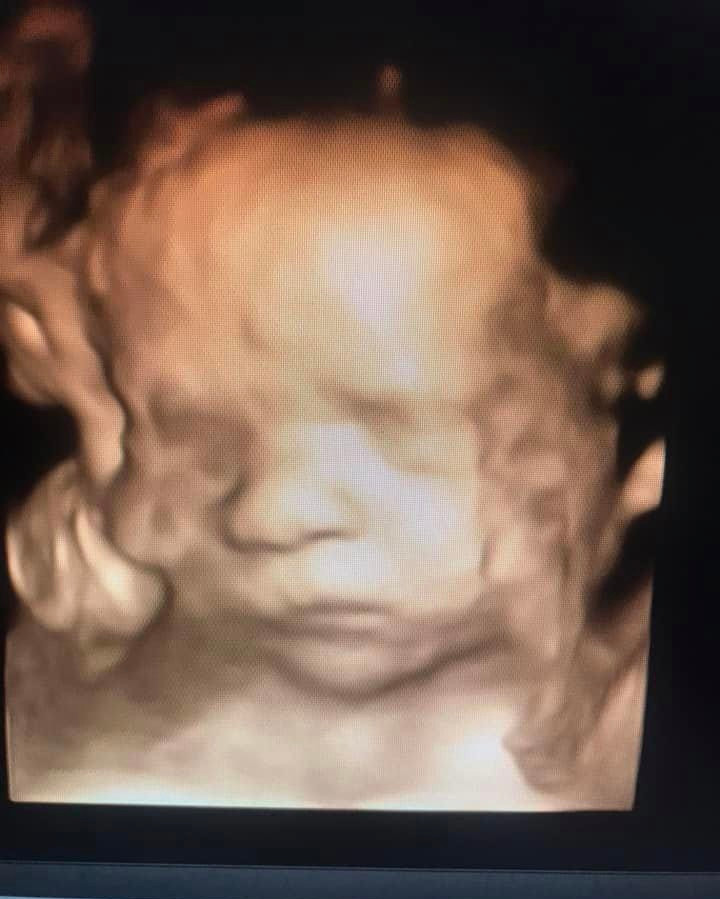

I will never forget walking out the doors of the OB/Gyn office one day in 2021. I occasionally work for Obstetricians and perinatologists in the area if needed. After a long day of scanning around 14 pregnant patients, I caught myself smiling as I got into my car to drive to the hospital where I work full time. On this particular day, I was able to show husbands and wives their baby’s heart beat for the very first time, or show cute profile pictures of their baby or tell them their baby has lots of hair or long eyelashes! I could go on and on! Seeing the joy on the parents to be faces brings me so much unexplainable joy! My heart feels like it could explode! I had a couple patients that day that came in to have their very first early ultrasound. Unfortunately, for those patients, the news was grim. I had to explain that there was no heart motion seen. As difficult as this is to explain to excited parents to be, I was able to comfort them, answer questions to the best of my ability, offer them pictures and give advice; as I, myself have experienced the loss of babies. As I left that day smiling, I thought to myself, I could do this all day for free! Then the lightbulb went on! Should I just start my own little side business? The thought of owning my own business scared the shit outta me. I’m not gonna lie. Haha! Well, my researching began! I started out looking up other private ultrasound places in and around the Orange County area. Much to my surprise, most of the people running these businesses and the techs performing the ultrasounds were not registered, licensed sonographers! They did not go to qualified schools, they did not have any experience working with Drs, clinics or at hospitals. To me, this is a disservice in the community. Our pregnant moms-to-be deserve better! And so it began………

I have been told that I am different than most ultrasound techs in that I engage with the patient, their significant other and I will include their kids if there are any. I will explain everything I am doing and answer as many questions as allowed. I try my best to make it an enjoyable, unforgettable moment and bonding with the baby. My goal in having my own little private ultrasound studio is to keep it very simple. No other techs other than myself scanning, no waiting rooms and no crossing paths with any other clients.